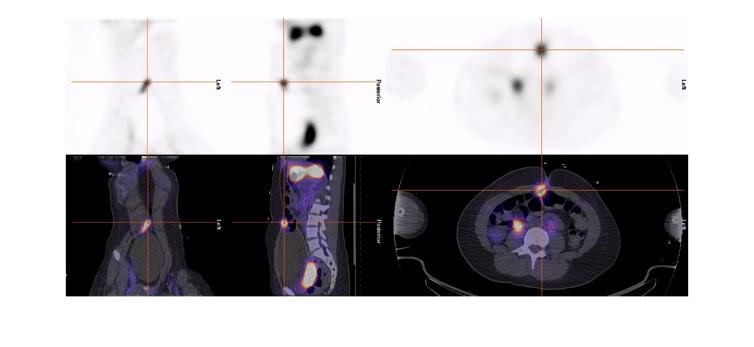

Figure 6 : Patient de 13 ans avec douleurs abdominales mais sans rectorragies. Mise en évidence sur la TDM diagnostic d’une image anormale à la fosse iliaque gauche. Scintigraphie effectuée avec préparation préalable avec famotidine po pendant 2 jours. Sur l’étude dynamique ( A ) apparition d’un foyer au niveau de la fosse iliaque gauche (flèche) de façon concomitante à l’estomac, soit vers la deuxième minute, avant les reins et la vessie qui sont démontrés respectivement à 5 et 9 minutes. Foyer (flèche) en augmentation sur le cliché planaire post miction ( B), confirmé avec la triangulation de l’étude SPECT-TDM où le diverticule est visualisé (C) et le rendu 3D (D).

Figure 7 : Adolescente admise avec hémorragie basse massive. Préparation avec famotidine intraveineuse. Mise en évidence sur l’étude dynamique ( A ) puis sur le cliché statique ( B ) d’un foyer ombilical augmentant en intensité et en taille (flèche). La relation du diverticule contenant de la muqueuse gastrique avec l’ombilic est bien démontrée sur le SPECT-TDM (C). La pathologie de la chirurgie effectuée dans la foulée via laparotomie et non laparoscopie étant donné les trouvailles a démontré un Meckel de 6 x 2 cm contenant de la muqueuse gastrique, avec aspect perforé associé à un canal omphalomésentérique de 0,5 x 0,5 x 0,5 cm. Moins de 4 heures se sont écoulées entre l’arrivée de la patiente à l’urgence et la chirurgie.